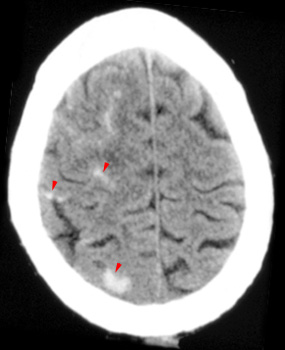

Question 6: Given the following head CT, the most likely diagnosis is: